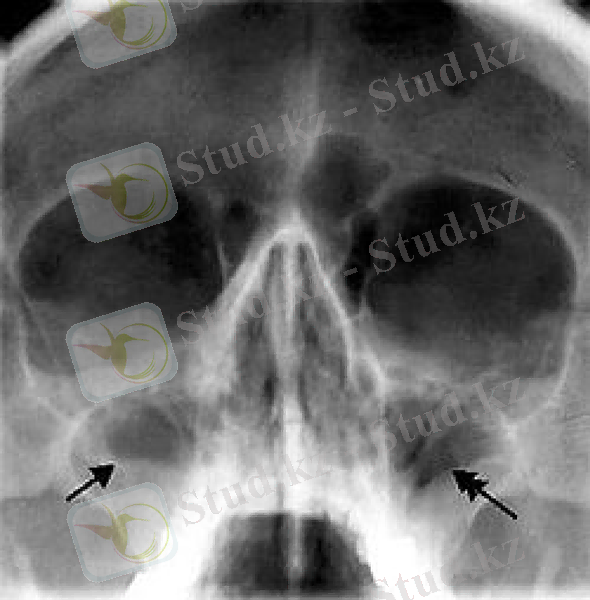

Диагноз клиникалық белгісіне қарап тексеруге мұрын қуысы шырышын қарау ( қабыну, ісіну, қуыс тесігінен іріңді бөлініс ) . Рентгенограммада гаймор қуысы қараяды. Мәлімет жетіспеген кезде басқа әдістерден гаймор қуысының пункциясы жасалады.